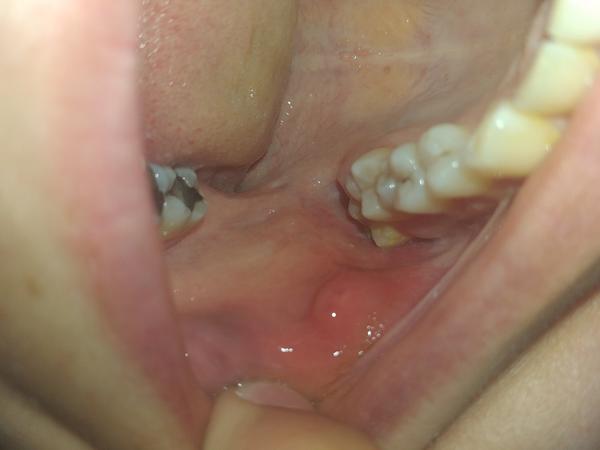

Žienky viete mi poradit co to môže byť?

Mne to príde ako zub

@viestta ale navrchu tej hrcky mam biele ako by aft

@2861994 nezahryzli ste si tam omylom? Vtedy to tiež býva take 🤷‍♀️